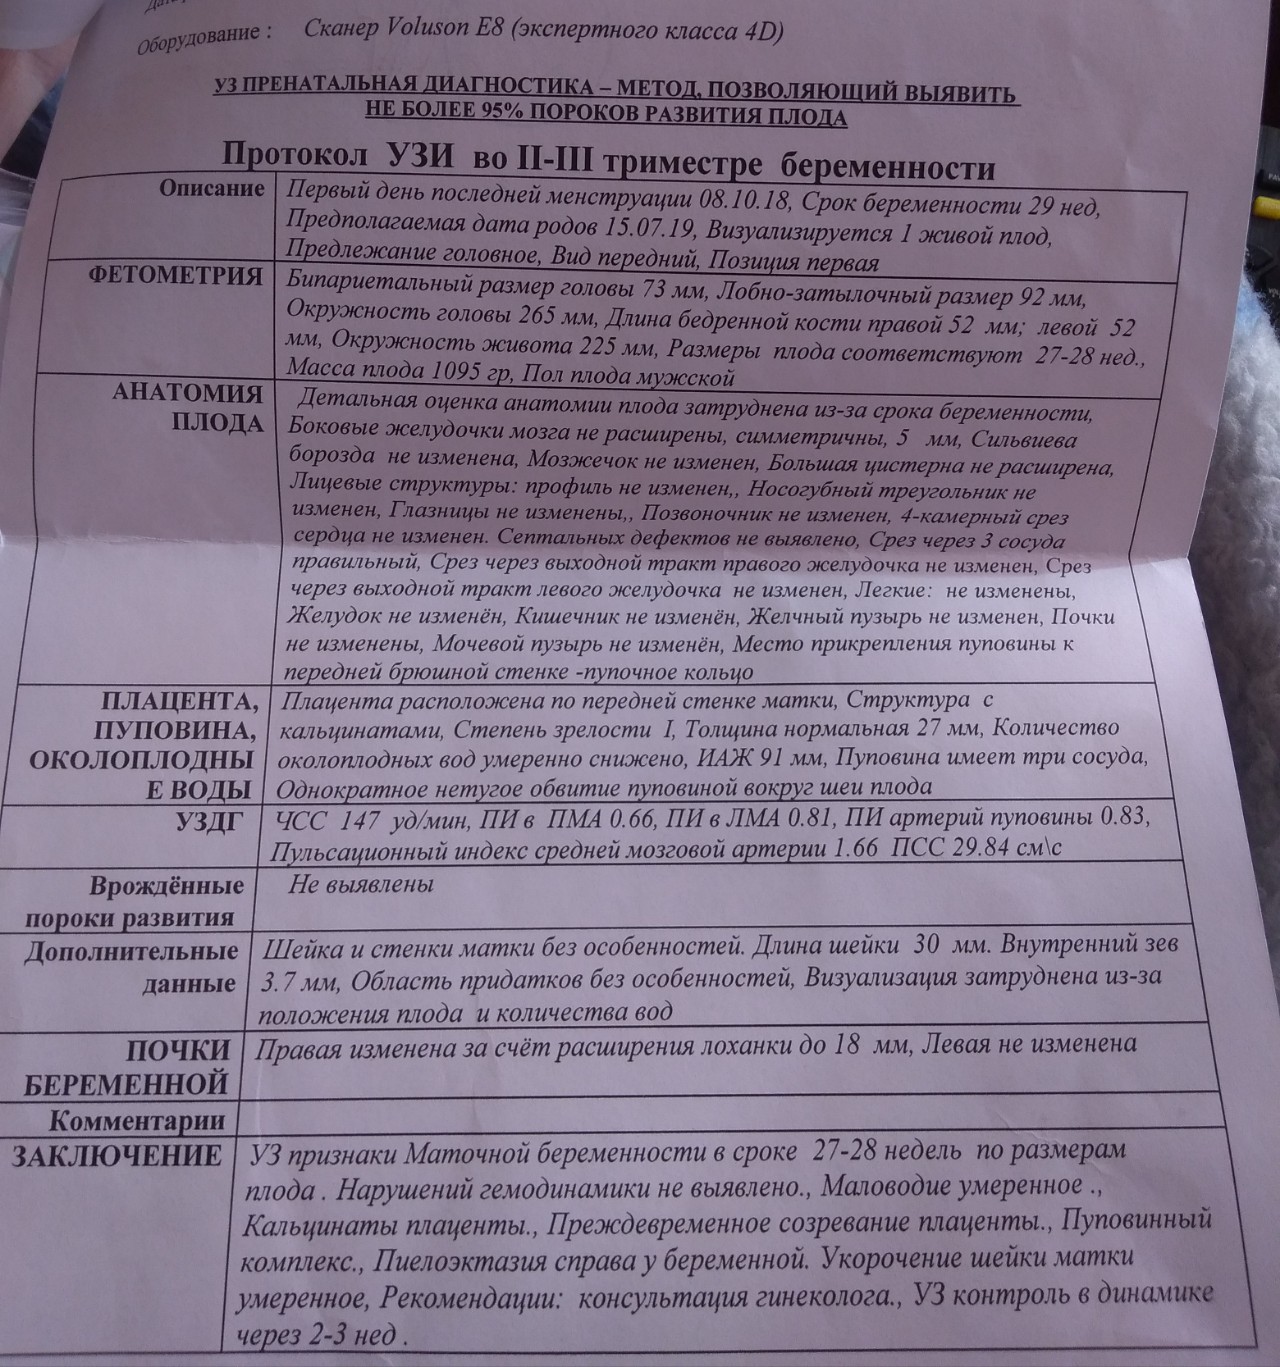

Нормы УЗИ 19-20 недель беременности

УЗИ на 35 неделе доплер норма

Норма ИАЖ В 35 недель беременности